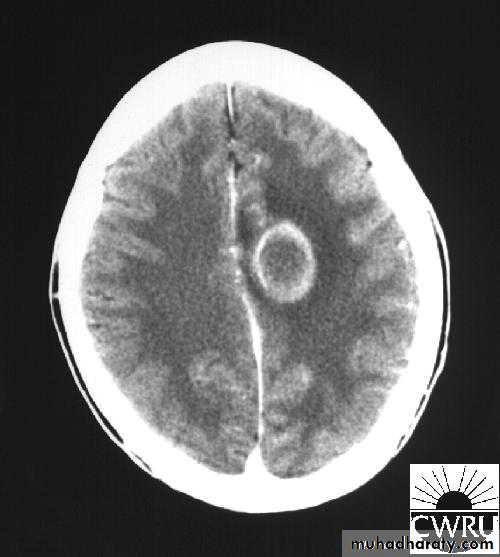

Brain Abscess

• B. Radiological Investigations:

• CT or MRI is the investigation of choice.

• CT Brain is performed with and without contrast.

• MRI is done with gadolinium enhancement.

• They will show a single (or multiple) space occupying lesion that is well delineated with an enhancing wall, with variable surrounding oedema.

Brain Abscess CT with contrast

Neurosurgery

• The differential diagnosis of a single brain abscess in CT or MRI is a solitary metastasis, primary brain tumour or cerebral infarction.

• The differential diagnosis of multiple brain abscesses is from multiple metastasis and tuberculoma.